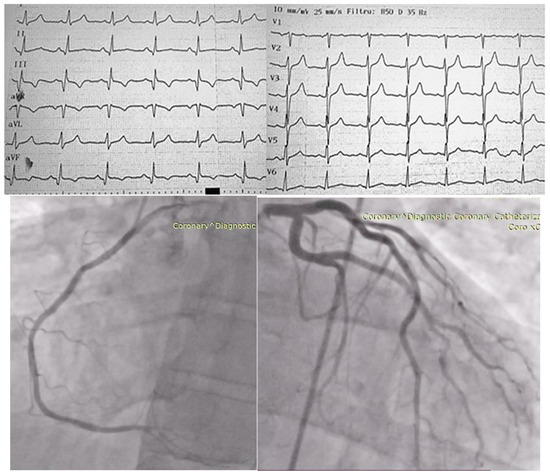

Particularities of a Cardiac Amorphous Left Ventricular Tumor in a Patient with Coronary Artery Disease—Diagnostic and Therapeutic Challenges: A Case Report and Literature Review

2. Case Presentation